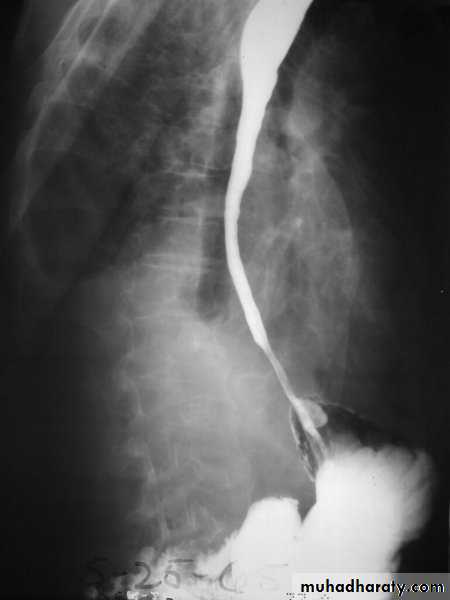

Barium swallow findings:

Tapered narrowing of the lower esophagus, esophageal body is dilated, aperistaltic and food-filled.Clinical features:

Chest X-ray: widening of the mediastinum, aspiration pneumonia.A barium swallow: tapered narrowing of the lower esophagus, esophageal body is dilated, aperistaltic and food-filled.